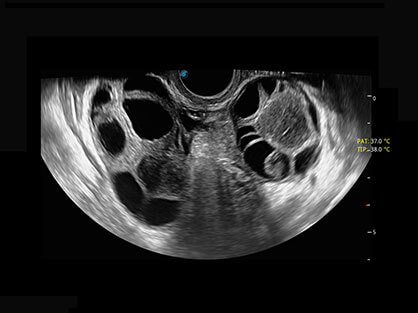

宽频带腹部凸阵探头和腹部容积探头、大角度腔内探头和腔内容积探头、独特的生殖专用曲柄探头,为妇产应用提供全面诊疗方案。

卵泡结构的自动识别和测量,可显示多组测量数据。

大角度腔内容积探头,可完整包络子宫及盆底结构,充分展示组织结构毗邻关系。